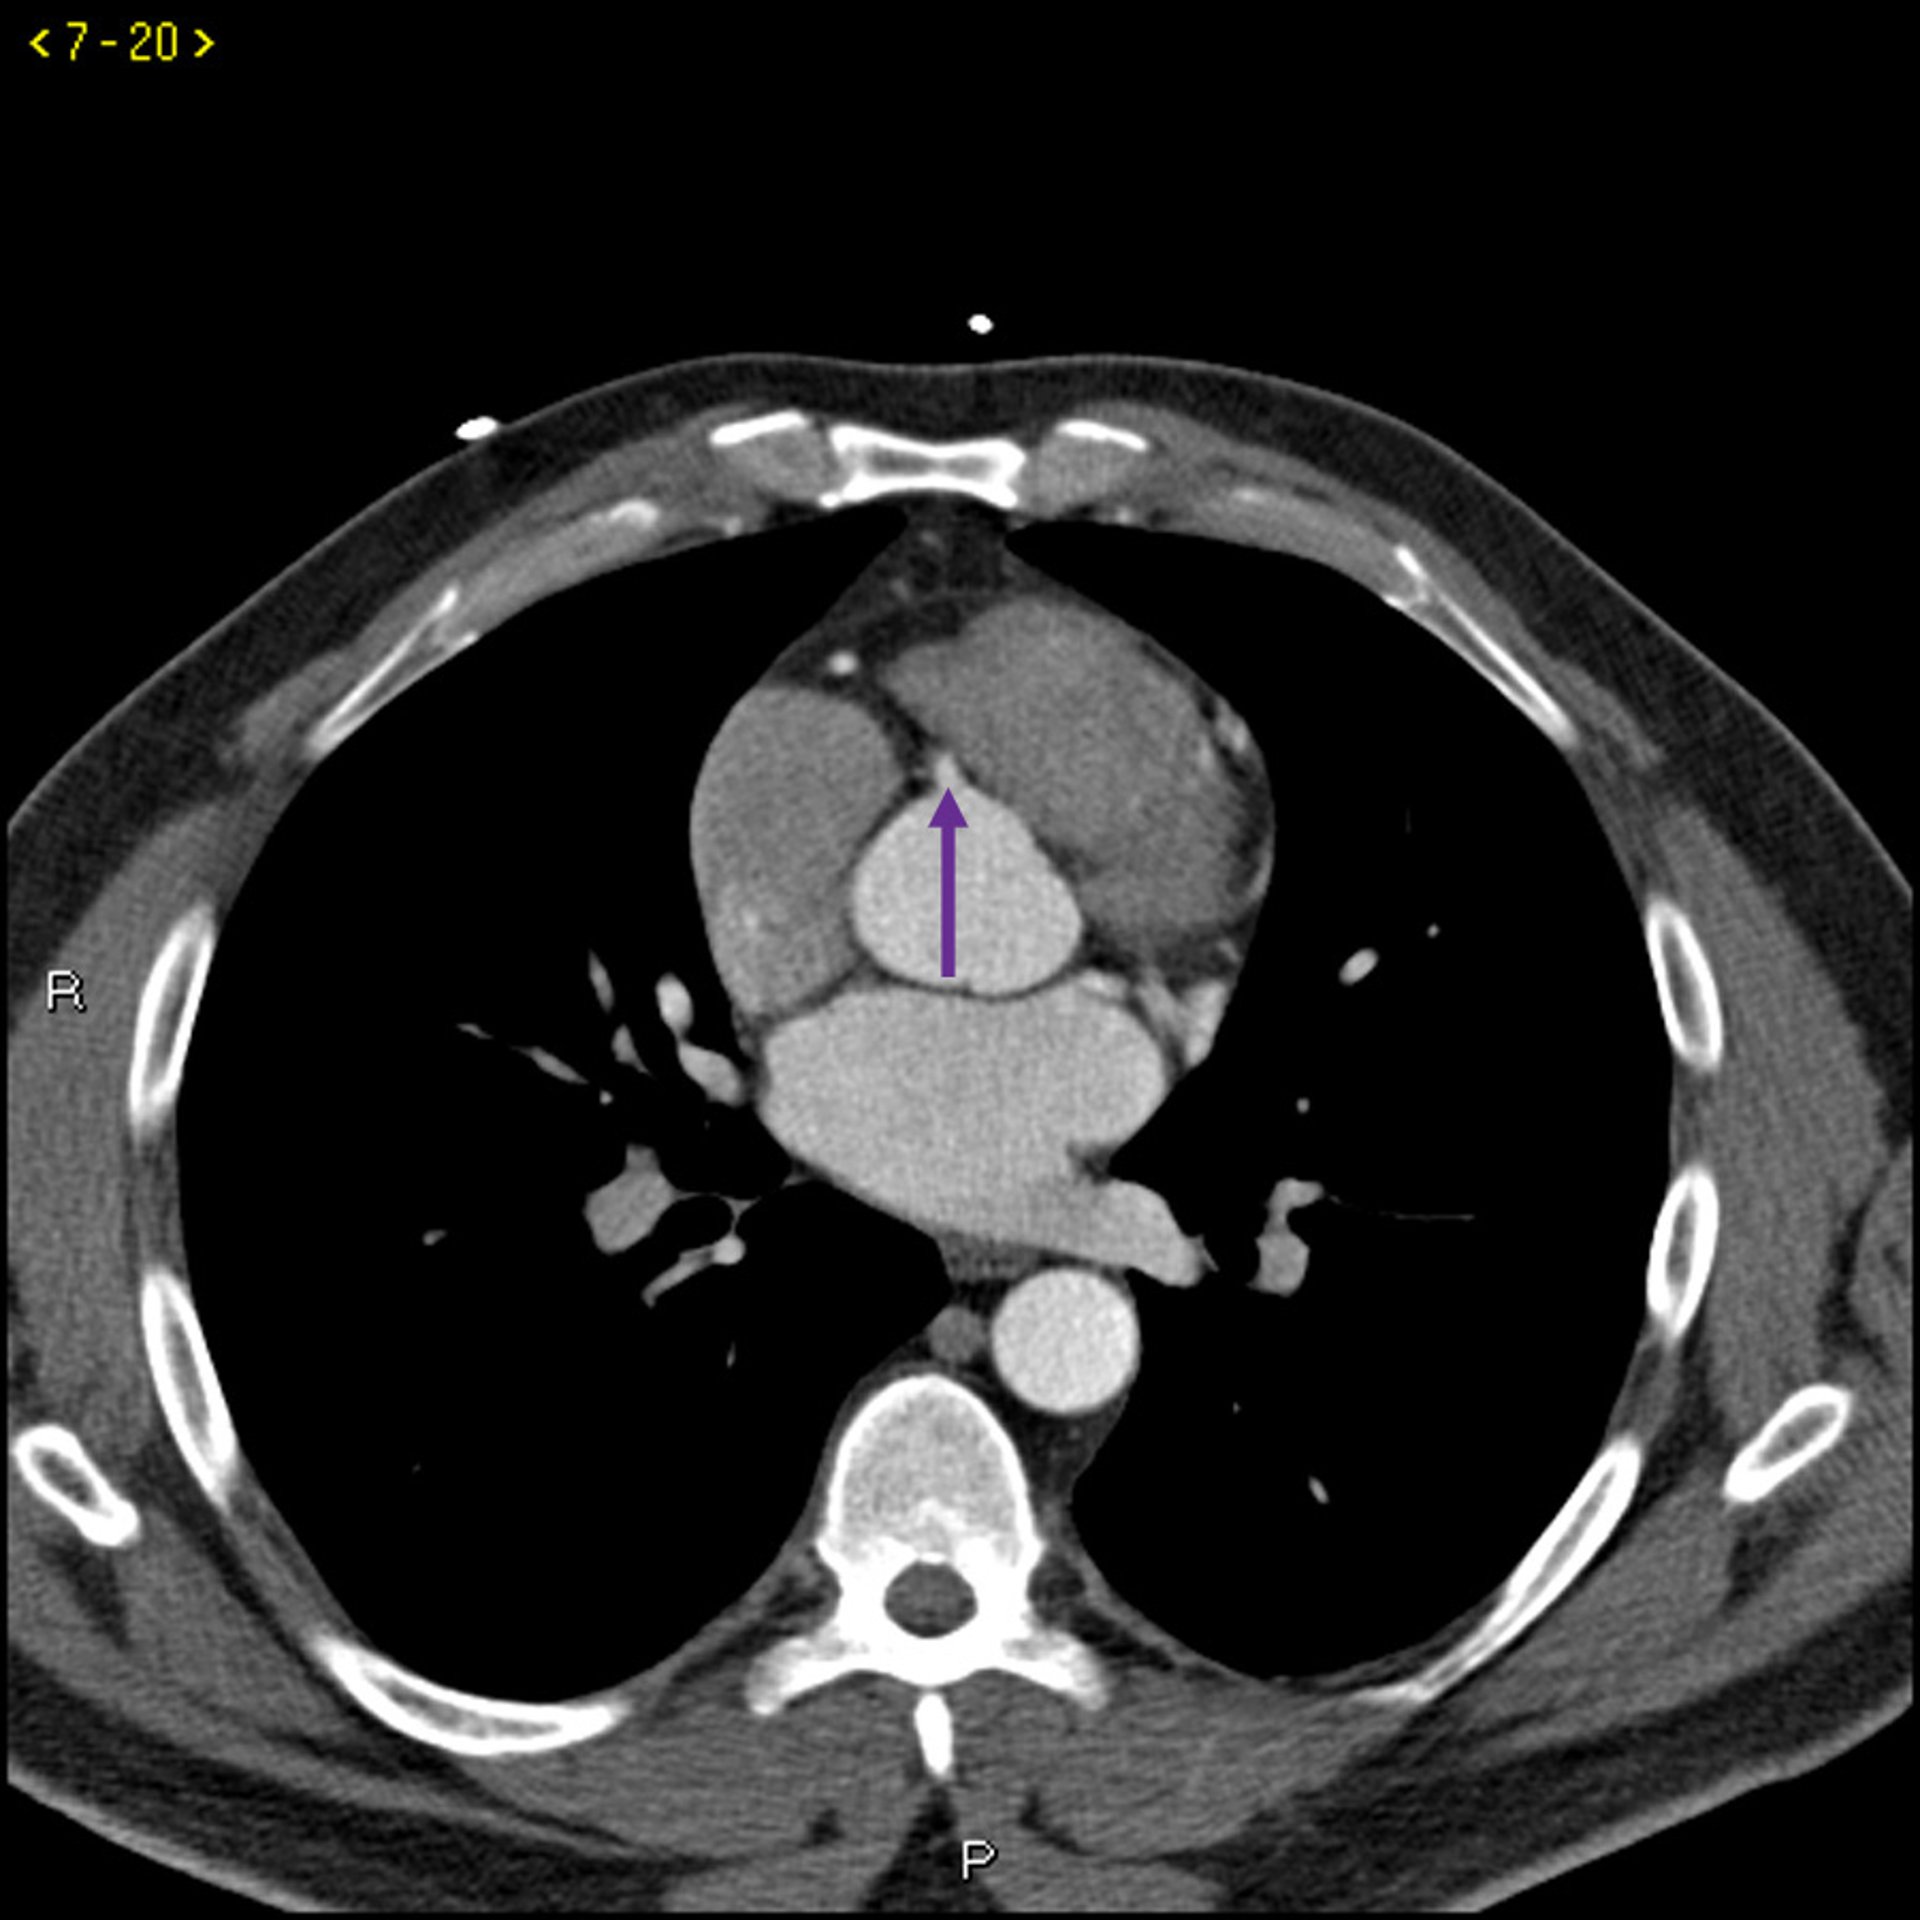

Kontrast CT zeigt normale Koronararterien - Folie 5

Dieses Kontrast-CT zeigt normale Koronararterien. Die linke Hauptleitung ist durch den roten Pfeil gekennzeichnet. Die linke anteriore absteigende Arterie und die linke Zirkumflexarterie sind durch den grünen bzw. blauen Pfeil und die rechte Koronararterie durch den lila Pfeil gekennzeichnet.